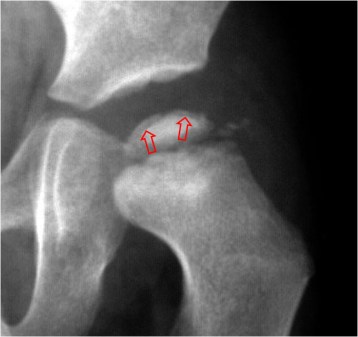

SIGNO DE LA SEMILUNA

Línea curva subcondral radiolucente cuya localización típica es la cara anterolateral de la cabeza femoral (aunque puede ocurrir en otras localizaciones) y corresponde a necrosis avascular. Esta lesión deriva en colapso de la superficie articular de la cabeza femoral.

En la imagen, este signo (flechas) en un niño con enfermedad de Perthes.